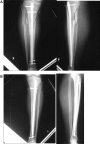

Posterior tibial stress fractures are more frequent than anterior tibial stress fractures, and they are considered to have a good prognosis for returning to sports; cases leading to a complete fracture are rare. A 17-year-old male involved in high school athletics middle-distance running had a 3-week history of pain with training. He was running up to 300 km/week on streets and cross-country in an even distribution. He had posterior tibial stress fractures, but despite the lower leg pain, he continued running. One year later, he was brought to the emergency department after having sustained an injury to the right lower leg while running in a middle-distance race; bilateral tibial stress fractures, with one side complete and the opposite side incomplete, had developed simultaneously. This relatively rare case of bilateral posterior stress fractures, with one side a complete fracture and the opposite side an incomplete fracture, that was treated surgically via exchange intramedullary nailing is reported. The patient could begin light jogging from 3 months after surgery and was without symptoms at 5 months after surgery. He could resume middle-distance racing after 1 year. Posterior tibial cortical fractures are more common and respond better to conservative treatment than anterior tibial stress fractures, and they are a common fracture type in runners. We believe that close, careful follow-up is necessary if patients continue excessive training.